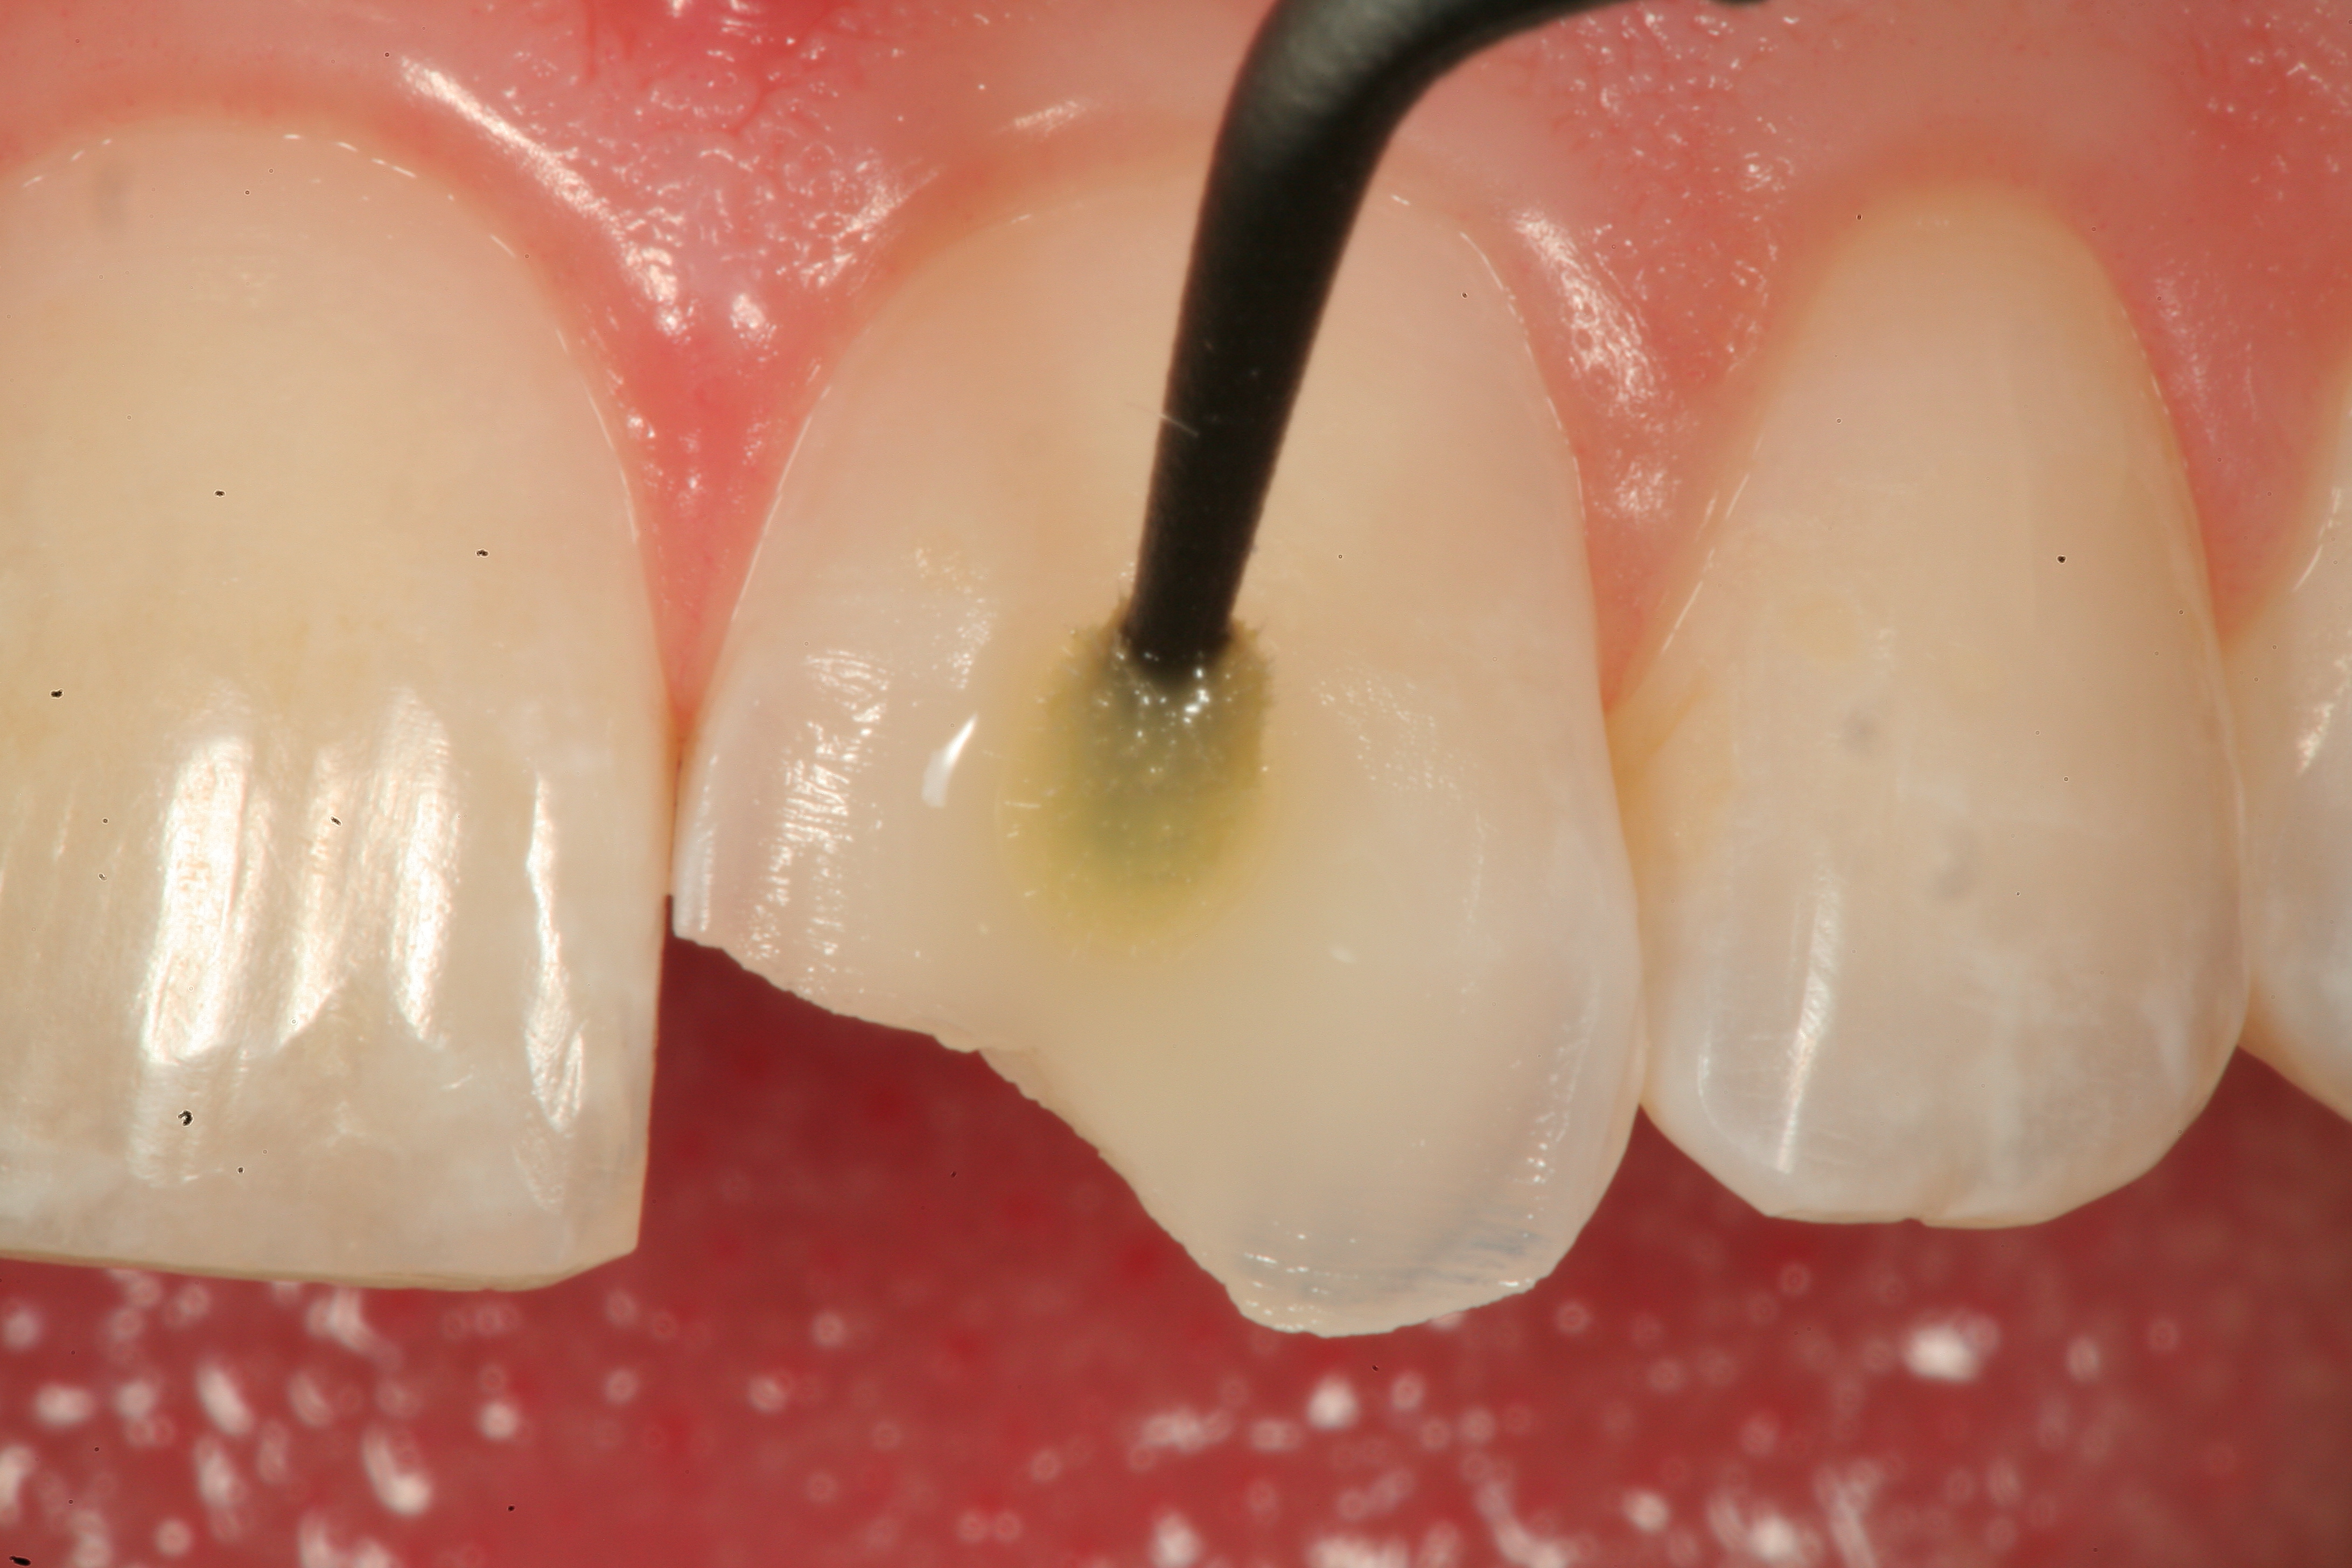

Fig 13. After placement of a bevel on the facial surface 2 to 3 mm from the position of the fracture, the enamel is etched and rinsed, and an adhesive resin is scrubbed into the prepared surface.

Figure 13